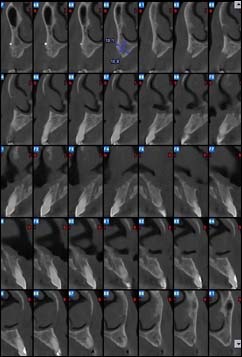

EXAMENS TOMOGRAPHIES VOLUMIQUES TYPE SCANNER OU CÔNE BEAM :

Dernière technologie à notre disposition, cette technique permet de voir en 3 dimensions des images de votre bouche et de mettre en évidence des pathologies ou des anomalies que les autres techniques ne permettent pas d’objectiver.

Reconstruction coronale